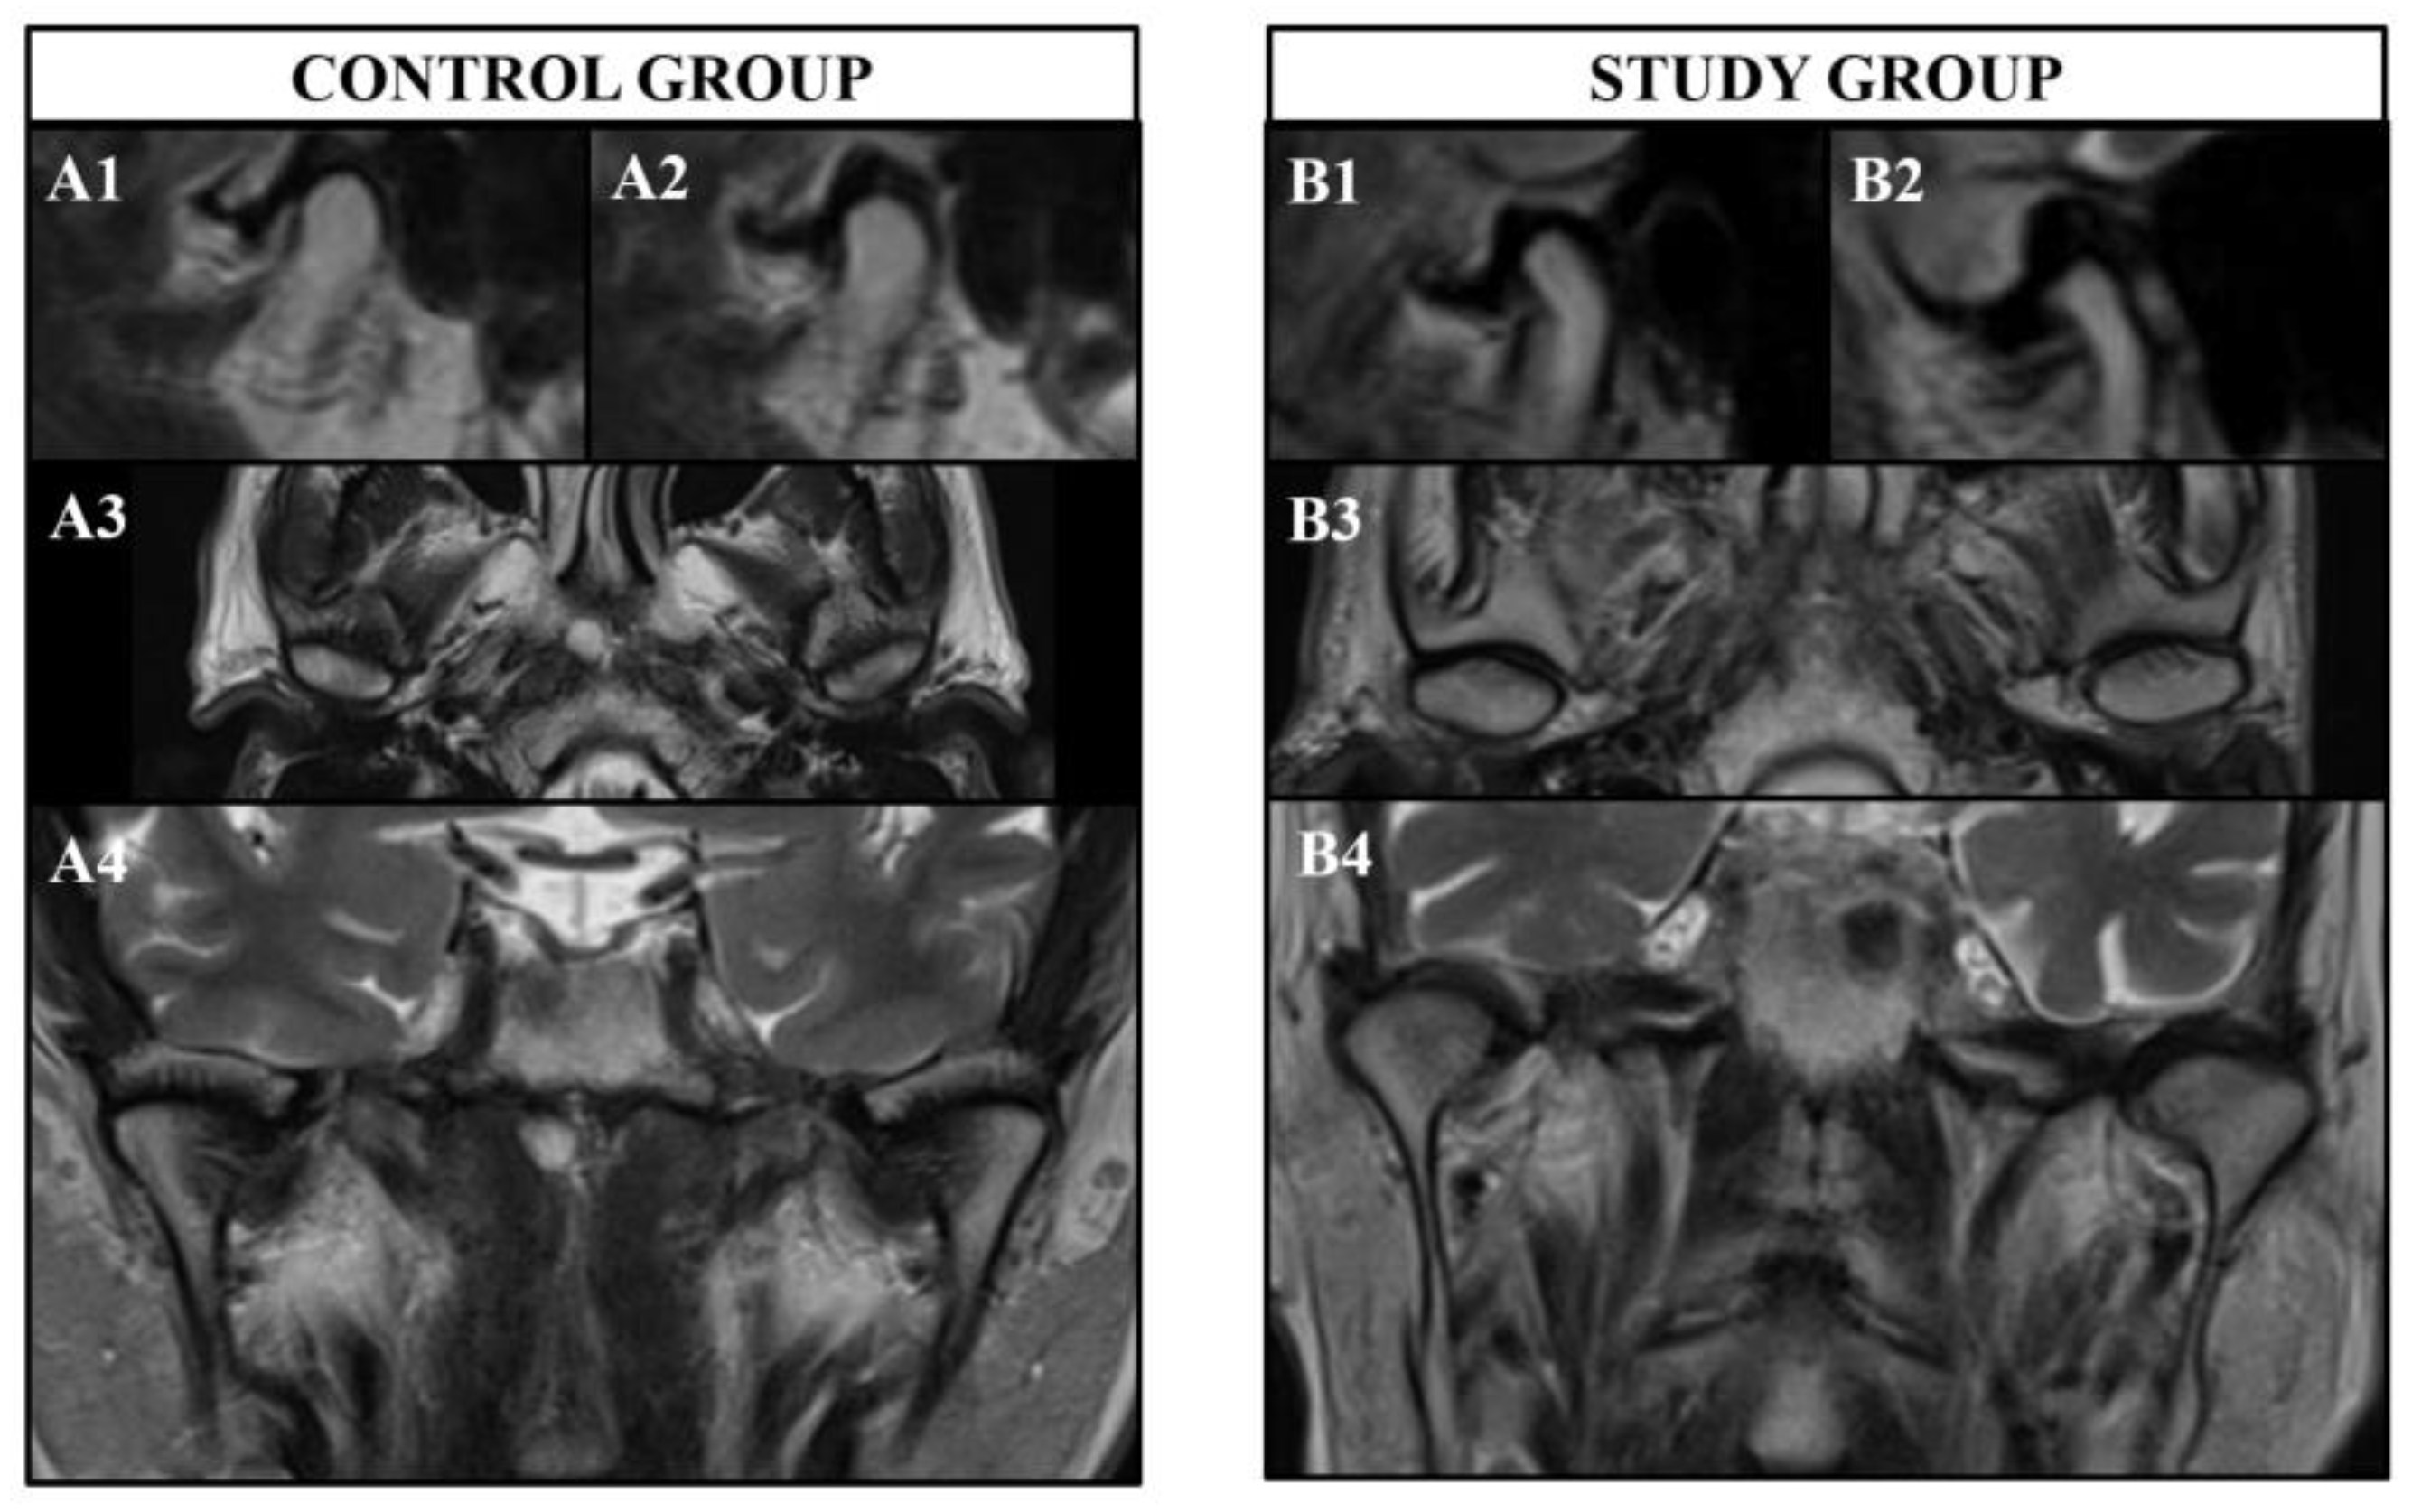

According to the results of the current study, healthy subjects showed morphological similarities and symmetry of the TMJ bilaterally in general (

Figure 4). However, only the long axis of the condyle showed asymmetry in healthy subjects. On the other hand, patients with PD showed morphological differences and asymmetry of the TMJ bilaterally regarding all parameters measured in the three different planes (

Figure 4). When the differences of both sides were compared between the healthy subjects and patients with PD, those with PD showed more asymmetrical TMJs in general except for the long axis of the condyle.